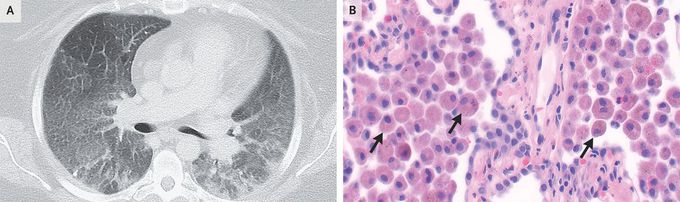

A 34-year-old woman with tobacco use disorder, severe obesity, and chronic hypoxemic respiratory failure of unknown cause was referred to the pulmonary clinic for worsening dyspnea and dry cough. She reported no history of environmental or occupational exposures, substance use, or fevers. Her oxygen saturation was 93% while she was receiving 3 liters of supplemental oxygen. On physical examination, breath sounds were quiet but vesicular. There was no clubbing of the fingers. Pulmonary-function tests showed mild restriction and a mild reduction in diffusing capacity. Computed tomography of the chest showed diffuse ground-glass opacities and areas of peripheral consolidation but no basilar reticulations or honeycombing (Panel A). The results of testing for autoantibodies and hypersensitivity pneumonitis were negative, and bronchoalveolar lavage was not diagnostic, so surgical lung biopsy was performed. The histopathological analysis showed interstitial fibrosis and extensive alveolar filling with pigment-laden macrophages on hematoxylin and eosin staining (Panel B, arrows). These findings were consistent with a diagnosis of desquamative interstitial pneumonia, a rare form of idiopathic interstitial pneumonia that is highly associated with cigarette smoking. A lung biopsy is necessary to make the diagnosis. Treatment with a smoking-cessation program and a tapering dose of glucocorticoids was initiated. At the 3-month follow-up, the patient’s symptoms remained unchanged as she continued to engage in smoking cessation.